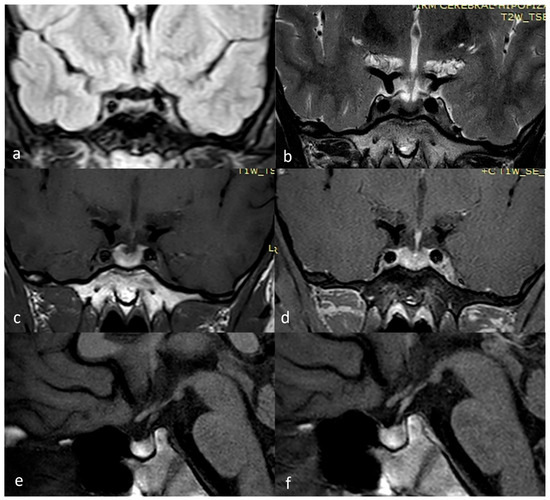

2. Case Presentation